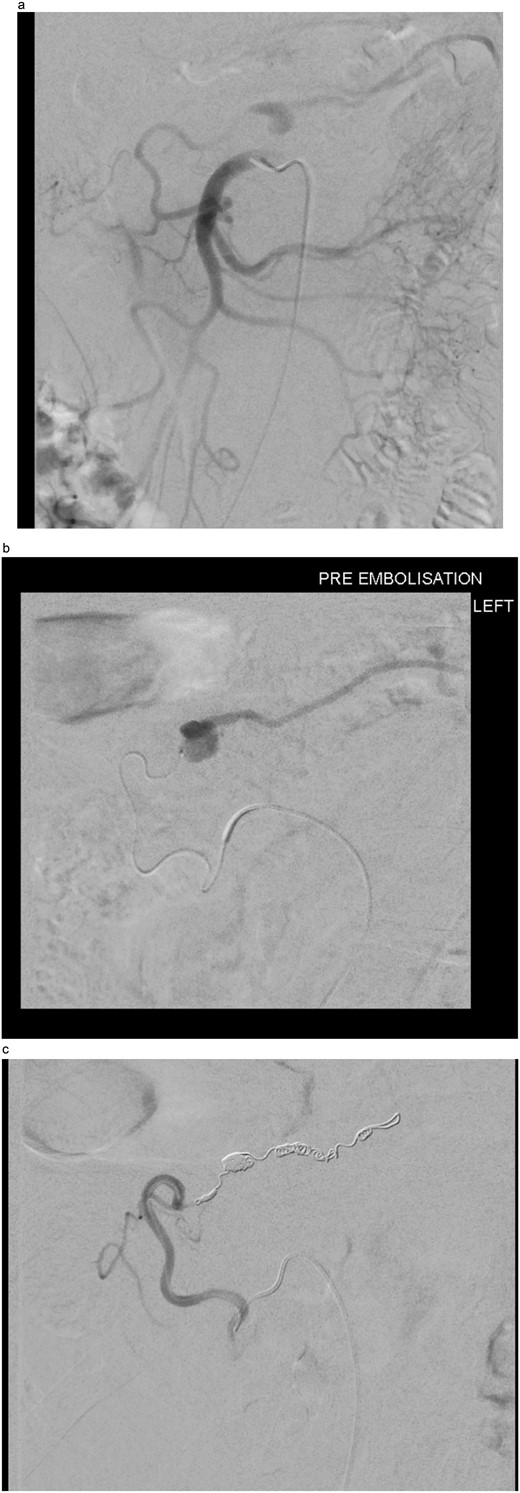

The two-week interval CTA showed that the pseudoaneurysm had increased in size to 2.1 × 1.8 × 1.8 cm (AP × TR × CC) (see Fig. 2). Whilst acknowledging the high risk of gut ischemia, the MDT agreed that intervention was necessary to avoid the risk of rupture. Eight weeks after initial pseudoaneurysm diagnosis, he underwent successful embolization of the MAoD. The embolization procedure was challenging due to tortuosity of the vessel and at the time, deemed too tortuous to stent on table, therefore embolization performed with microcoils (see Fig. 3). He remained clinically asymptomatic with a soft abdomen and had an overnight stay with the general surgery team on standby. His lactate remained insignificant overnight. He opened his bowels and managed a normal diet and was therefore discharged home the following day.

Interval CT angiogram demonstrating enlargement of the false aneurysm (2.1 × 1.8 × 1.8 cm).